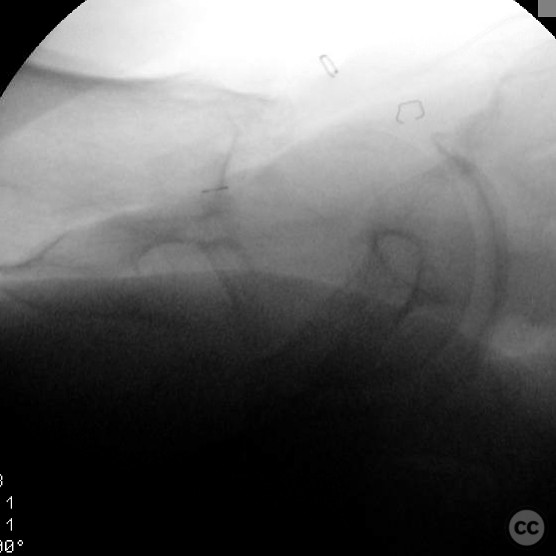

Patient positioning:  The patient was positioned supine on a fracture table to facilitate closed reduction and percutaneous fixation under fluoroscopic guidance.

Anatomical surgical approach:  A percutaneous approach was utilized, involving small stab incisions for the insertion of guide wires and cannulated screws. Fluoroscopic imaging was employed to ensure proper alignment and fixation.